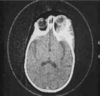

Cryptococcus can cause what kind of infections?

● Pulmonary infection

● Meningitis ( after it spreads from the lungs to the brain. )